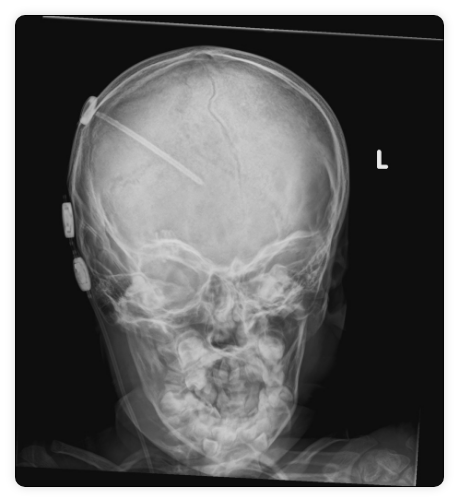

Paciente portador de válvula de derivación ventrículoperitoneal